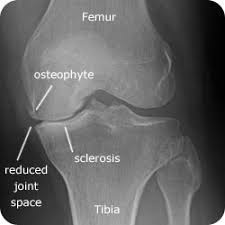

Dalam kajian lain yang dilakukan pada 2007, beberapa sebatian antioksidan seperti vitamin E, omega 3 dan vitamin C dapat mengekalkan ketebalan sel-sel tulang rawan yang dikaji menggunakan pemeriksaan MRI. Dalam kes osteoarthritis, kebanyakan pesakit mengalami kenipisan sel-sel tulang rawan sehingga menyebabkan ruang dalam sendi lutut menjadi sempit dan pesakit berasa sakit dan dengan sendi berbunyi apabila digerakkan.